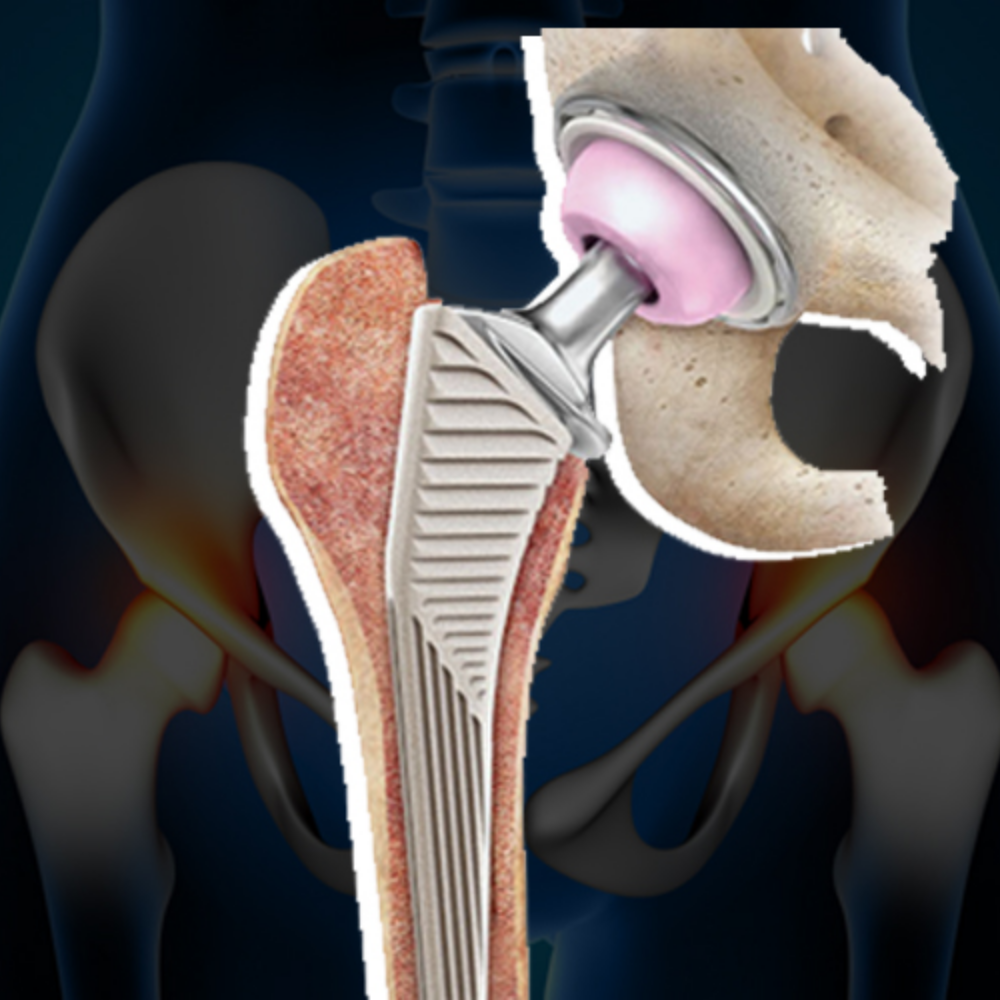

Replaces the damaged hip joint on one side with an artificial implant.

Recommended for patients with severe pain and functional limitation in one hip.

Both hip joints are replaced in a single surgical plan.

Recommended when both hips are severely affected.